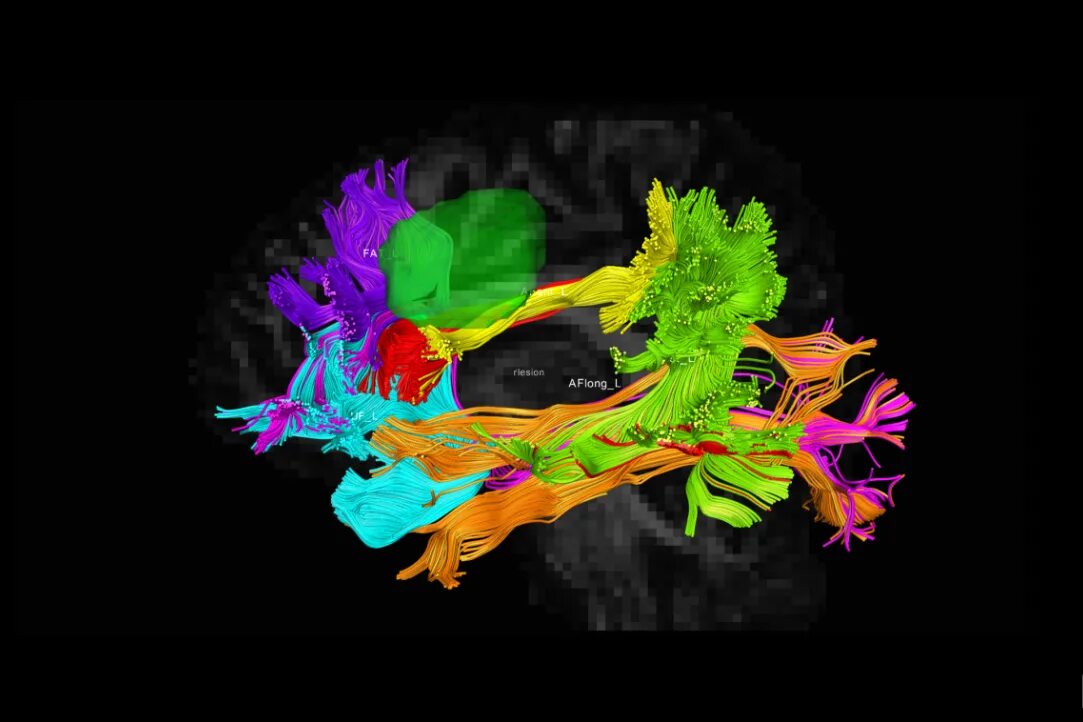

Diffusion tensor